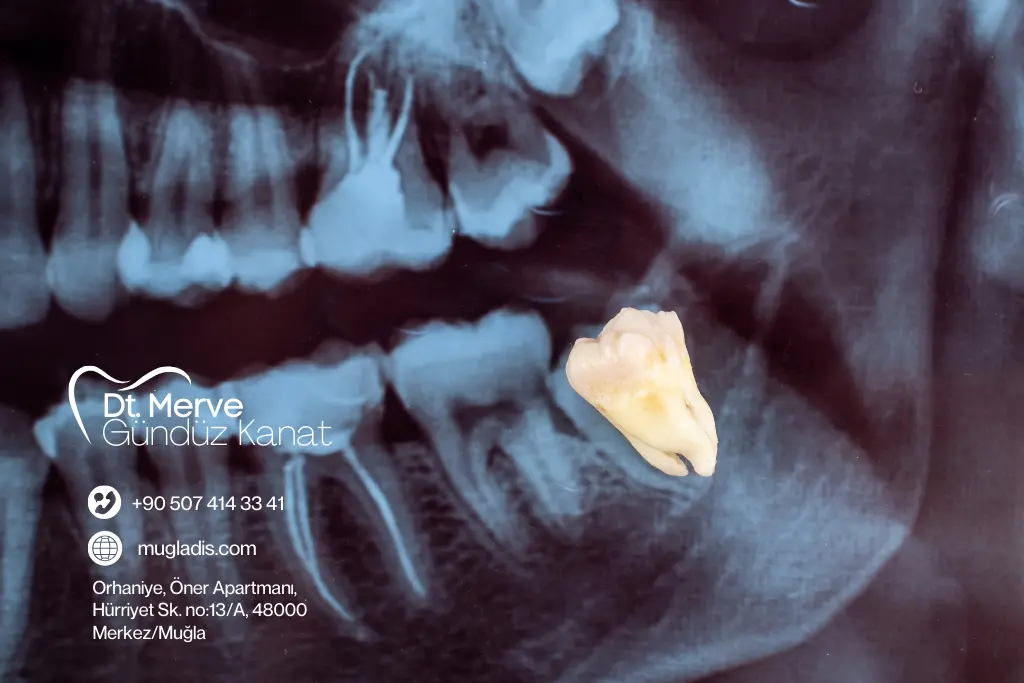

20’lik Diş Çekimi İşlemi

Normal sürmüş diş: Kısa sürede kolayca alınır.

Gömülü diş: Küçük cerrahi işlemle çıkarılır.

Tüm işlemler lokal anestezi altında, ağrısız şekilde gerçekleştirilir.